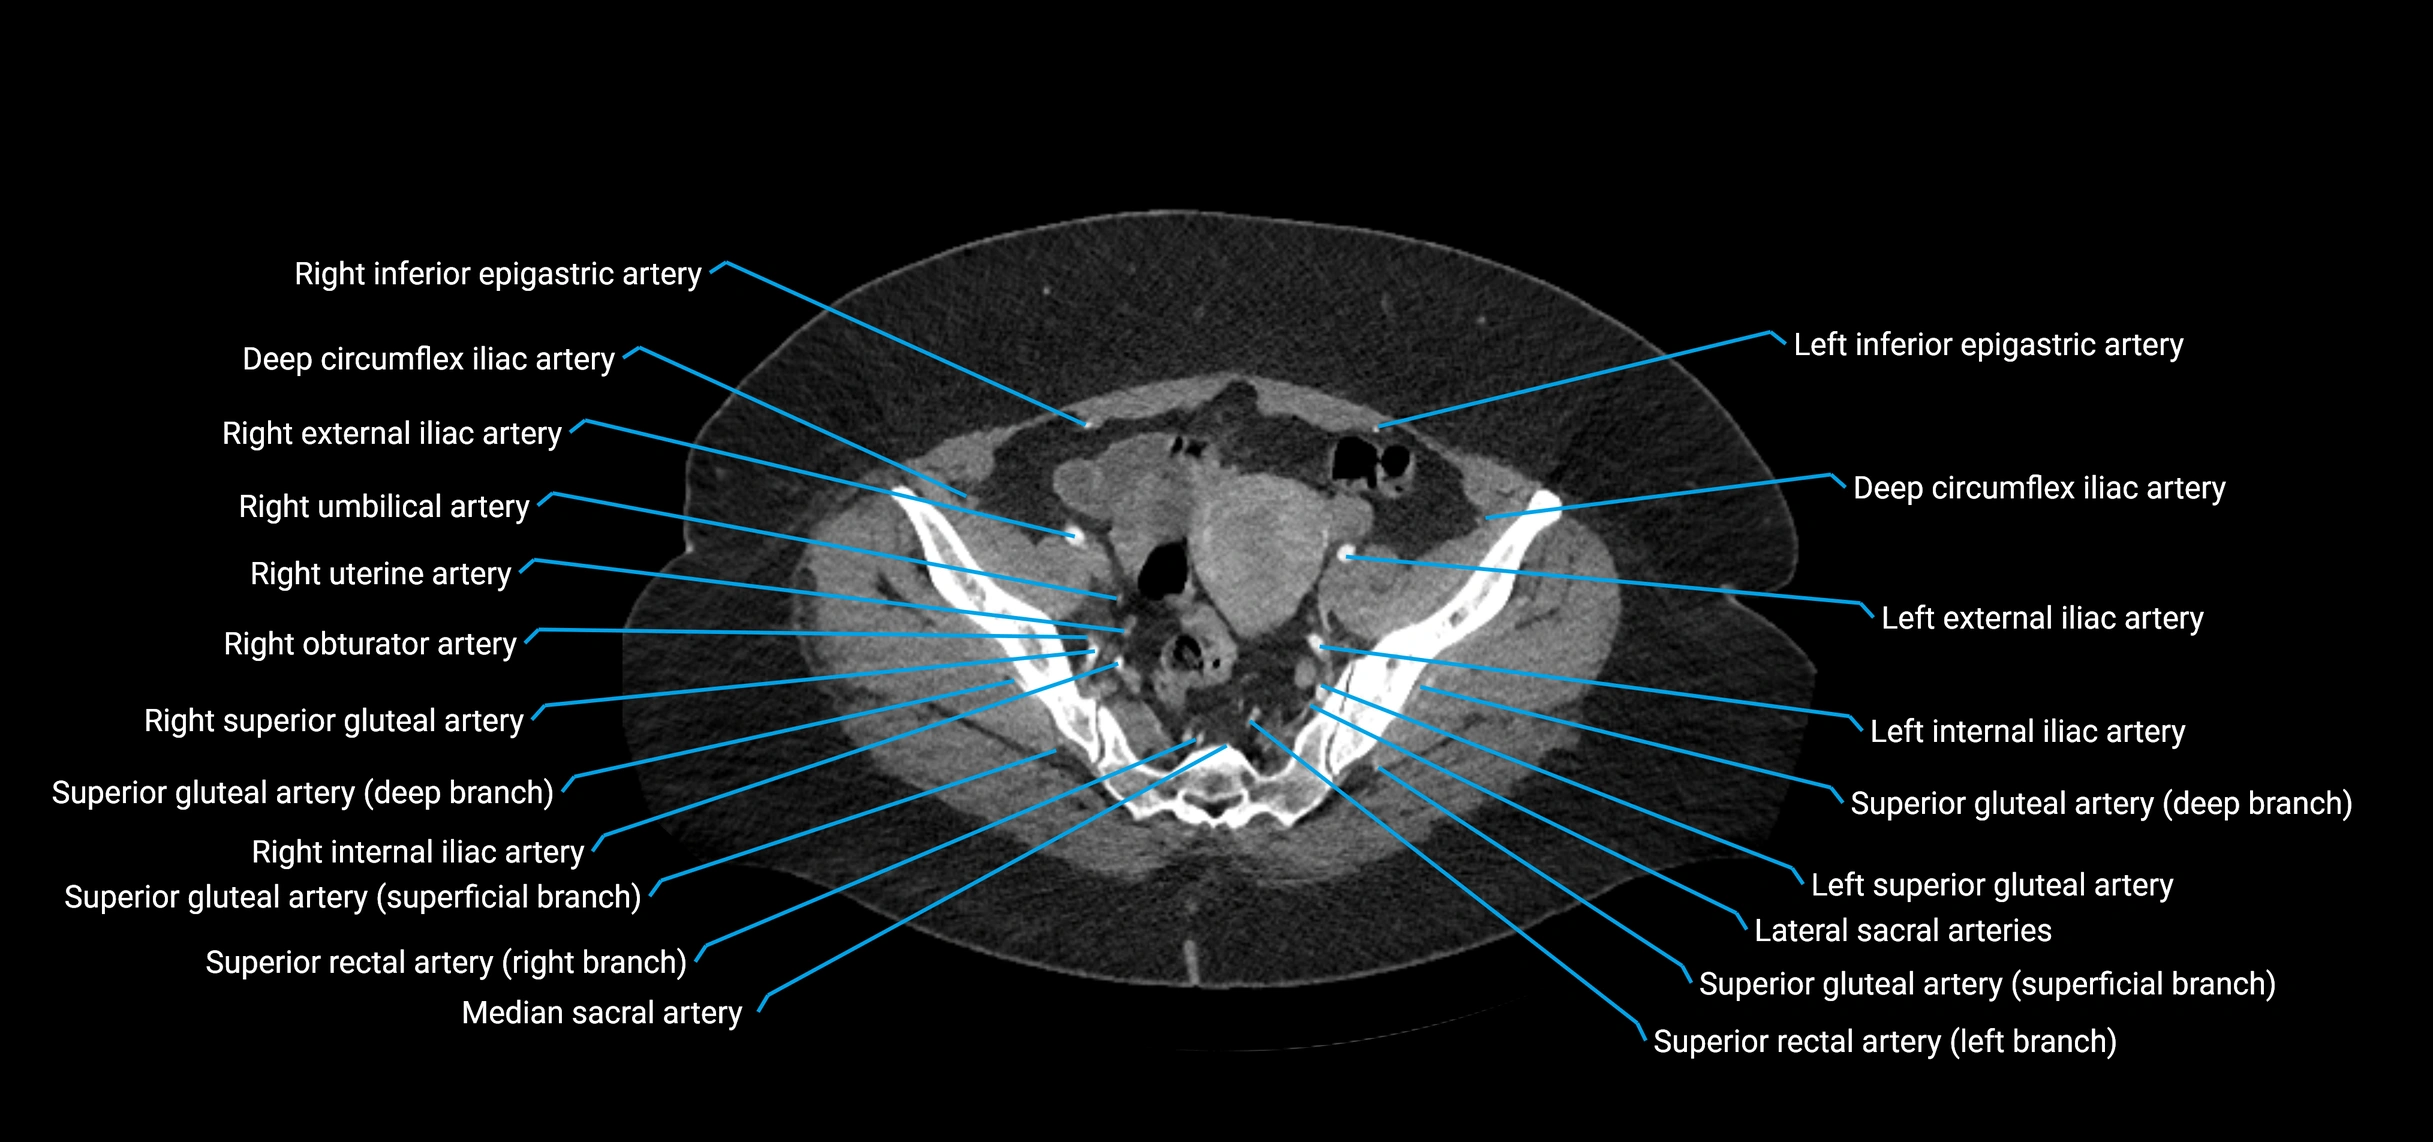

• Terminal branches: right and left common iliac arteries

Contrast-enhanced CT (CTA):

• Gold standard for abdominal aortic imaging

• Provides excellent detail of lumen, wall, aneurysm, thrombus, and branch vessels

• Multiplanar and 3D reconstructions help in aneurysm measurement, stent graft planning, and dissection evaluation